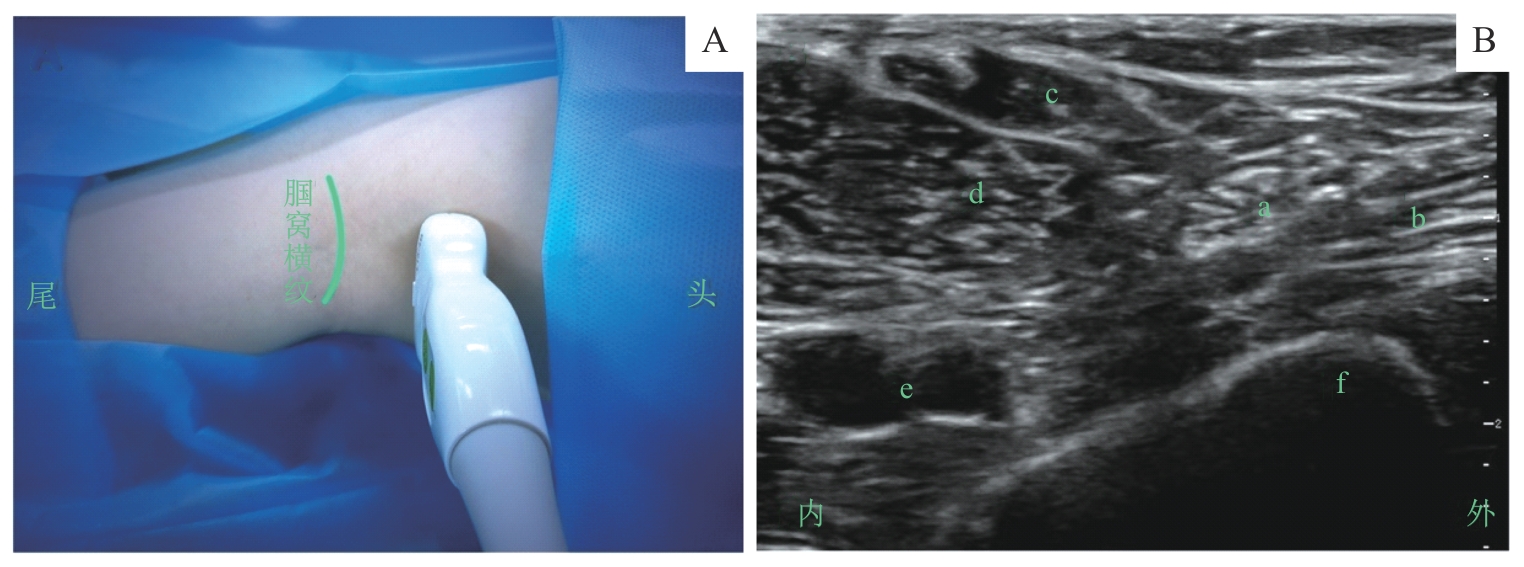

图4 腘窝坐骨神经阻滞的超声定位和影像Note: A. 超声探头体表扫描定位/Surface scanning for ultrasound probe positioning. B. 探头处于图A位置时的腘窝坐骨神经超声影像/Ultrasound image of the sciatic nerve in the popliteal fossa obtained with the probe positioned as shown in figure A. a—坐骨神经/sciatic nerve; b—股二头肌/biceps femoris muscle; c—半腱肌/semitendinosus muscle; d—半膜肌/semimembranosus muscle; e—腘动、静脉/popliteal artery and vein; f—股骨/femur.

Fig 4 Ultrasound positioning and imaging of the sciatic nerve block via the popliteal fossa